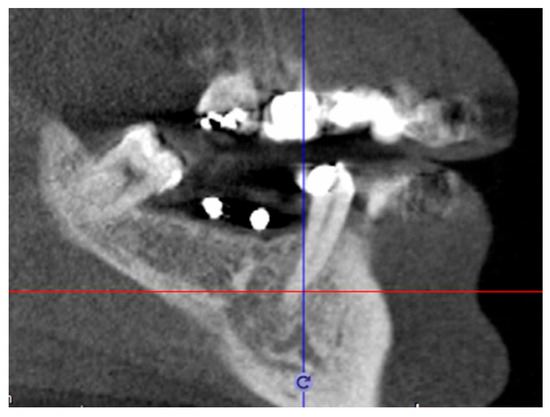

CBCT taken with template | Definitive patient selection Elegibility criteria: fixture position confirmed by CBCT |